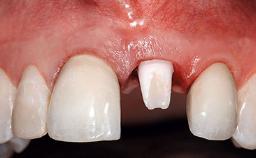

A 32-year-old female Caucasian patient with a compromised maxillary right central incisor was referred to us by a general dentist. Her chief complaints were discomfort and mobility of tooth 11 with unsatisfactory esthetics due to discoloration. The patient reported a previous trauma, some years earlier, as the origin of pathology on the afflicted tooth. Anamnesis was negative for any other dental or periodontal pathology in the remaining dentition. The patient did not take any medication and reported to be a light smoker (5–10 cigs/day). She had high esthetic expectations of her treatment. The extraoral examination revealed a high smile line with full exposure of her maxillary teeth and surrounding soft tissue in the area between the second premolars.

Soft Tissue Anatomy Intact Defective

Soft Tissue Contour and Volume Slightly compromised